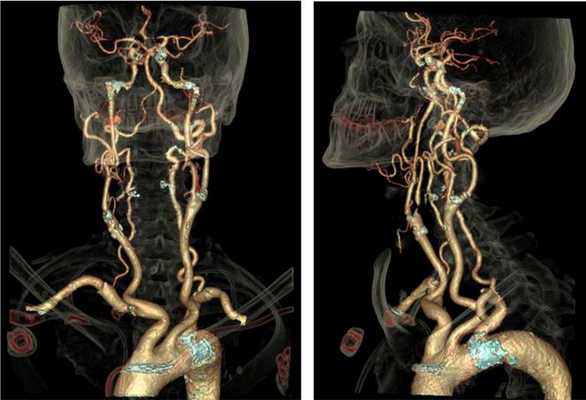

На томограммах четко прослеживается архитектоника сосудов исследуемой области

КТ-ангиография сосудов шеи с контрастом незаменима при травмах: скорость получения результата и отличная визуализация сосудистых катастроф, повреждений костных структур и нервных тканей позволяют быстро определить тактику ведения пациента. Большинство патологических процессов протекают генерализованно (атеросклероз, аутоиммунные заболевания), поэтому необходимо исследовать одновременно сосуды головы и шеи на предмет характера поражения и степени выраженности заболевания. На томограммах можно увидеть: